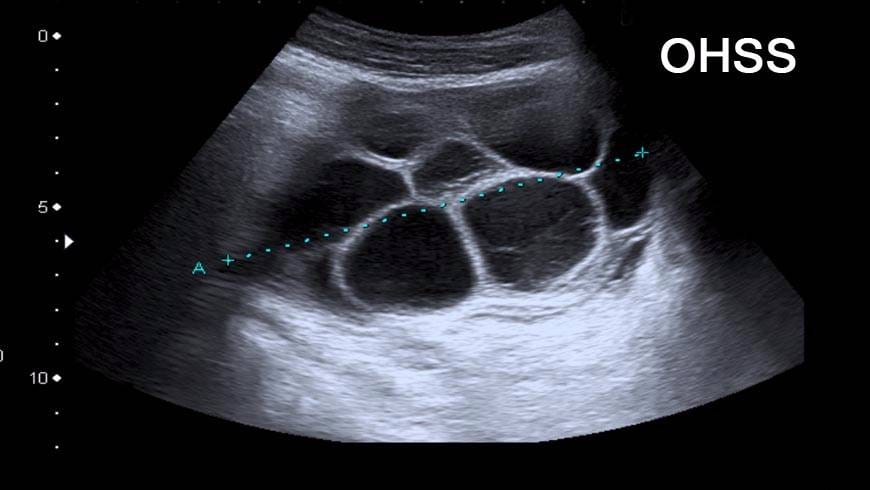

(OHSS, Extensive (hyper) stimulation of the ovaries) OHSS is a condition which may happen during IVF (In vitro fertilization) or intrauterine insemination (iui) treatment when the ovaries over react to… Continue Reading Ovarian Hyperstimulation Syndrome (OHSS)